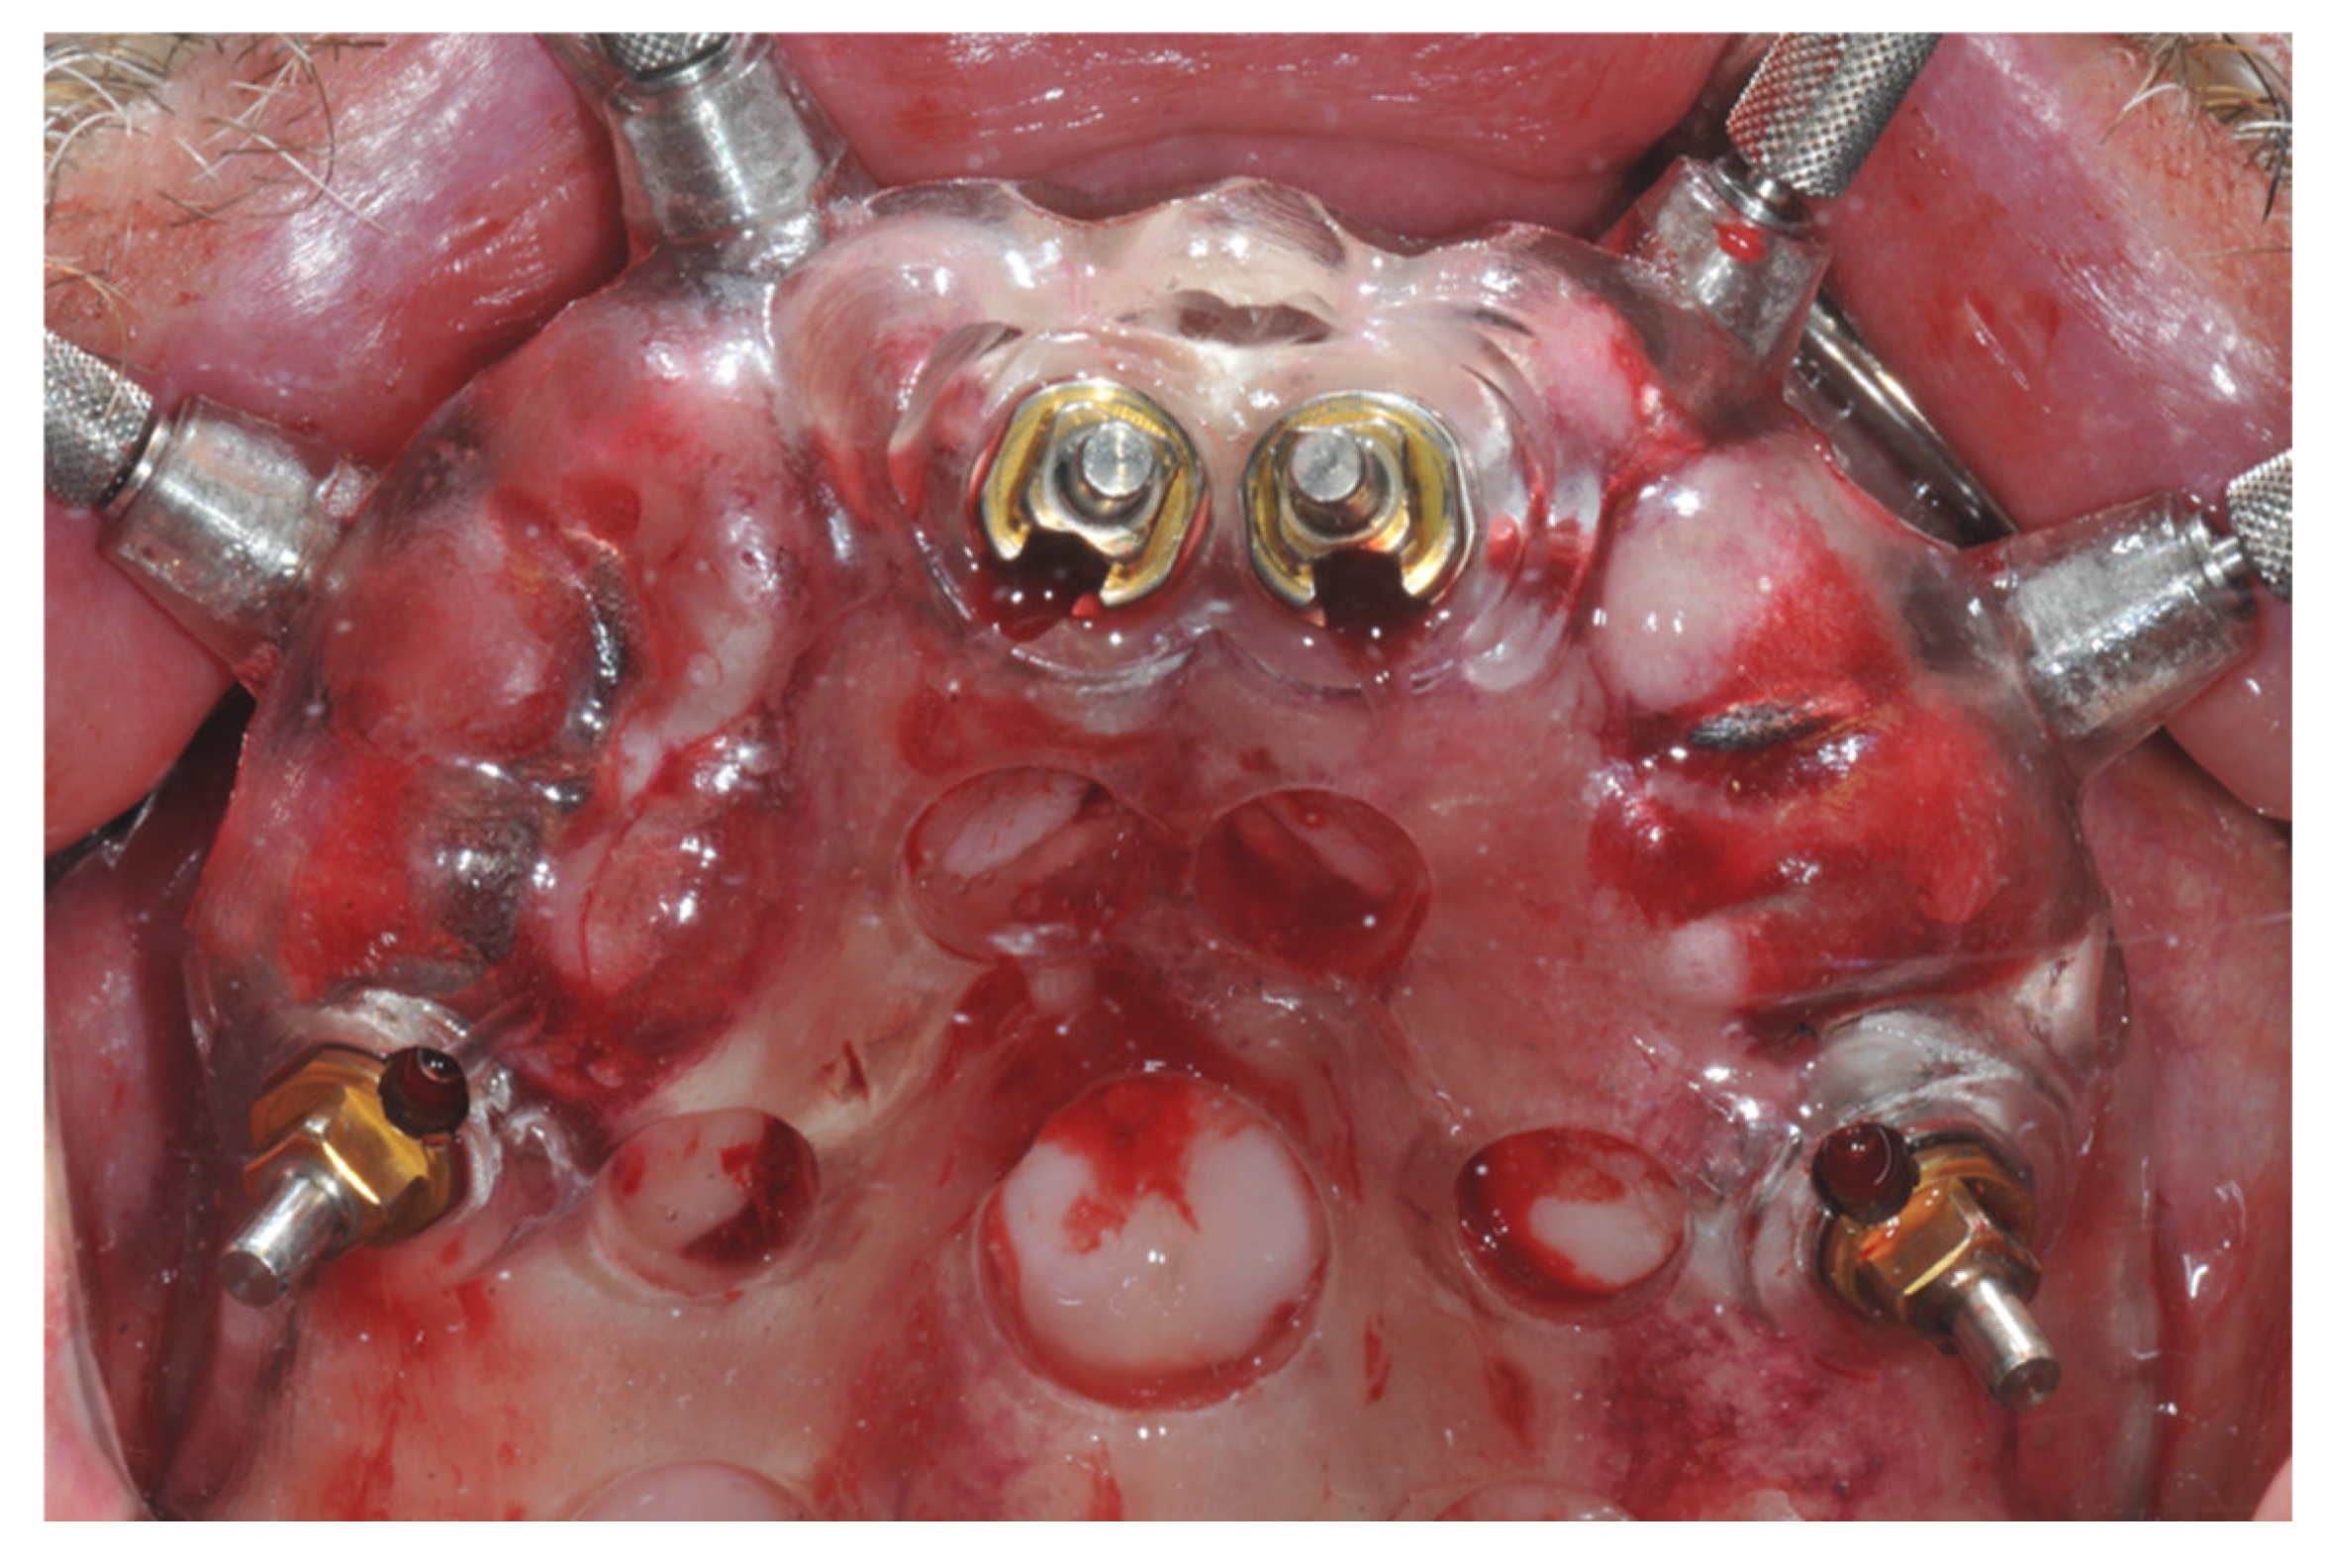

2. Materials and Methods